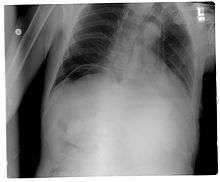

| Frontal chest X-ray. The air bubble below the right hemidiaphragm (on the left of the image) is a pneumoperitoneum. | |

Pneumoperitoneum is pneumatosis (abnormal presence of air or other gas) in the peritoneal cavity, a potential space within the abdominal cavity. When present, it can often be seen on radiography, but small amounts are often missed, and CT scan is nowadays regarded as a criterion standard in the assessment of a pneumoperitoneum.[1] CT can visualize quantities as small as 5 cm³ of air or gas. The most common cause is a perforated abdominal viscus, generally a perforated peptic ulcer, although any part of the bowel may perforate from a benign ulcer, tumor or abdominal trauma. A perforated appendix seldom causes a pneumoperitoneum.